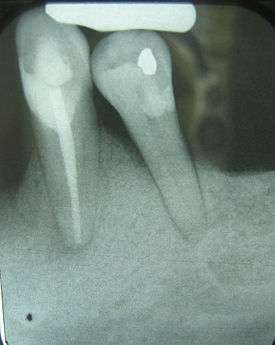

Crown-to-root-ratio is the ratio of the length of the part of a tooth that appears above the alveolar bone versus what lies below it.[1] It is an important consideration in the diagnosis, treatment planning and restoration of teeth, one that hopefully guides the plan of treatment to the proper end result.

These terms can also be used to refer to the clinical sense of the words, as relative crown and relative root, by describing how much tooth remains surrounded by bone. As the inflammation associated with periodontal disease causes the bone to resorb and disappear, revealing more of the root structure, the effective crown height in relation to the effective root height is reduced and the prognosis shifts from favorable to unfavorable.

Clinically, the anatomical definitions don't really matter; what is important in terms of support for the teeth within the bone is how much of the teeth remain embedded; this is where the crown-to-root ratio becomes important.

The natural crown-to-root ratio is thus termed a favorable crown-to-root ratio, because the root system existing within the surrounding bone is more than sufficient to support the tooth under normal physiologic stresses. After some bone loss is incurred, though, and more root structure is visible outside of the supporting bone, not only is there less effecive root support, but there is an increased height of revealed tooth structure that this now diminished submerged root is responsible for supporting. In a way, then, each millimeter of lost bone contributes, for example, to a millimeter of less support and a millimeter of more structure to support. As can be extrapolated, this can easily become a very serious problem once three, four or five millimeters of bone have been lost due to periodontal disease.[3] The minimum crown-to-root ratio necessary is 1:1; any less support provided by the roots drastically reduces the prognosis of the tooth and its restoration.